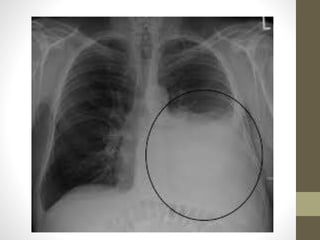

Diagnosis

1- chest X-ray:

-loss of costophrenic angle

- atleast 250 ml must accumulate to be seen